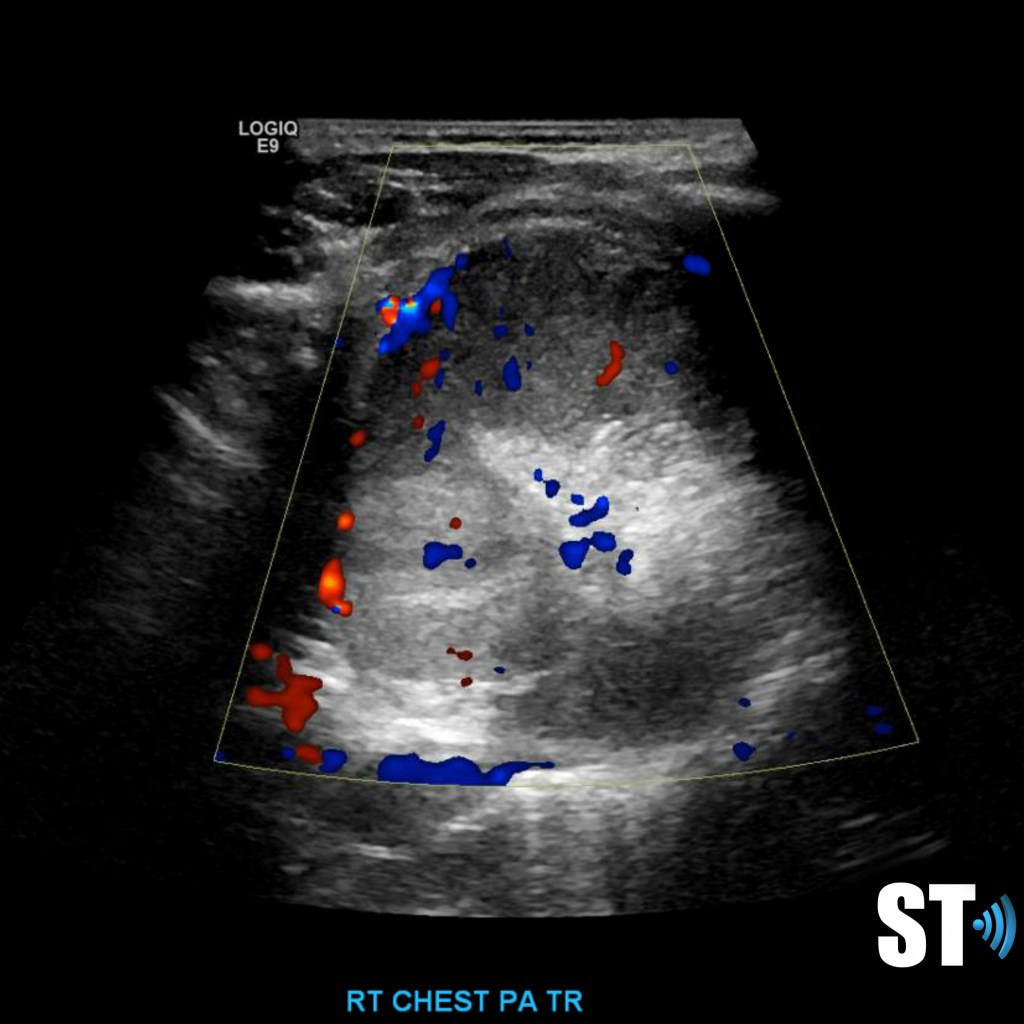

Color doppler will show blood flow through the pulmonary vasculature.

In alveolar consolidation the lung parenchyma takes on the appearance of liver echotexture, “hepatization”. There may be air bronchograms present in consolidated tissue which appears as hyperechoic air bubbles with reverberation artifacts. Color doppler will show blood flow through the pulmonary vasculature.